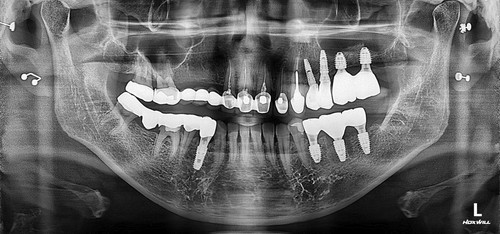

저희 치과에 오신 거는 발치한 날로부터 약 3주가 지난 상태로 오셨는데 발치한 치과에서는 한달이 안 되었기 때문에 더 기다려 볼 것을 권유 받으셨었습니다. 그런데 환자분이 제가 구강상악동누공에 대하여 작성한 포스팅을 보시고 저희 치과를 방문하시게 되었습니다. 보통 발치한지 3주가 되면 구강상악동천공의 단계를 지나서 구강상악동누공의 상태로 발전하게 됩니다. 내원 당시에 찍은 시티에서 10mm 이상의 천공이 확인 되었고 막아 놓았던 비흡수성 차례막을 제거하니 자연 치유될 정도의 천공이 아닌 걸로 확인하고 상악동누공폐쇄술을 시행하기로 하였습니다.

상악동누공폐쇄술이 성공하면 그 다음 단계로는 치조골 이식과 임플란트 식립을 해야 하는데 간혹가다 일반적인 상악동거상술에 비하면 누공이 있었던 부위는 상악동점막과 잇몸살이 유착되어서 힘든 경우가 많습니다. 물론 폐쇄술을 시행하면서 상악동에 뼈이식을 동시에 하는 것도 하나의 방법이 될수 있겠으나 성공했을 때 뿐만 아니라 누공폐쇄술이 실패했을 때를 가정한다면 통상적으로 동시 뼈이식을 시행하기에는 다소 위험성이 따르는 것이 사실입니다. 그래서 이 환자분은 안전하게 단계적으로 진행하기로 하였으며 누공폐쇄술이 성공한 후에 상악동 측방거상술을 시행하였고 이식한 뼈가 충분히 굳은 후에 임플란트를 식립하였습니다.

임플란트를 식립한 후에는 통상적으로는 3개월 후에 임플란트 보철물이 들어가는데 환자분의 사정으로 치과 내원을 못 하셔서 약 5개월 후에 오셨는데 왼쪽 아래 치아의 뿌리 부위의 충치가 발견되어서 아래 치아는 발치하면서 식립하는 즉시식립을 해 드렸습니다.

보통 하악에 임플란트 식립하면 2개월 이내에 치아가 들어가는데 마찬가지로 환자분 사정으로 못 오시다가 6개월이 지나서야 위,아래 임플란트 머리가 들어가고 마무리 할수 있었습니다.